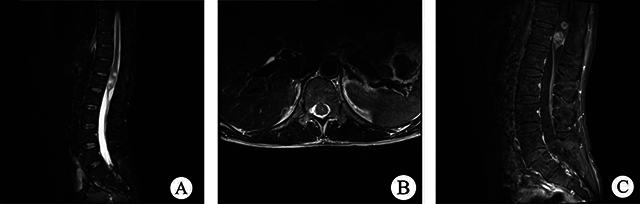

脊髓柔毛细胞星形细胞瘤(PA)是一种罕见疾病,具有不典型的临床和影像学特征,一般仅限于病例报告。我们分析了2010年1月至2021年7月期间收治的12例脊髓PA患者的临床表现、影像学结果、治疗和预后随访,并回顾了相关文献。放射学评估,尤其是磁共振成像,有助于提供有效的诊断信息。本文讨论了该疾病的诊断和鉴别方法,试图为更全面的术前评估做出贡献。

Spinal pilocytic astrocytoma (PA) is a rare disorder with atypical, clinical and imaging characteristics, and generally limited to case reports. We analysed the clinical manifestations, imaging findings, treatment and prognostic follow-up of 12 patients with spinal PA admitted from January 2010 to July 2021, and reviewed the relevant literature. Radiological assessment, especially magnetic resonance imaging, can help to provide effective diagnostic information. The diagnosis and differentiation of this disease is discussed in an attempt to contribute to a more comprehensive preoperative assessment.